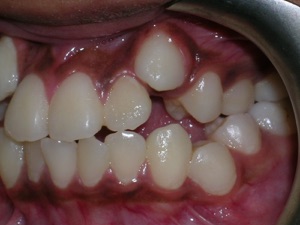

Here again we used a “Nance” holding arch. Look at some photos while the braces are on.